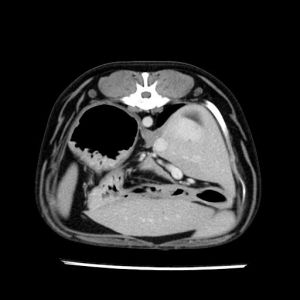

La lesione focale epatica , la ceus,la Tac e il chirurgo .